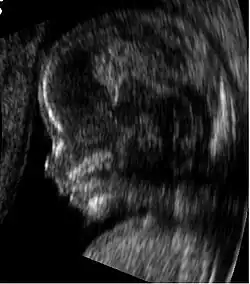

Profil d'un fœtus de 14 semaines

Échographie au premier trimestre de la grossesse